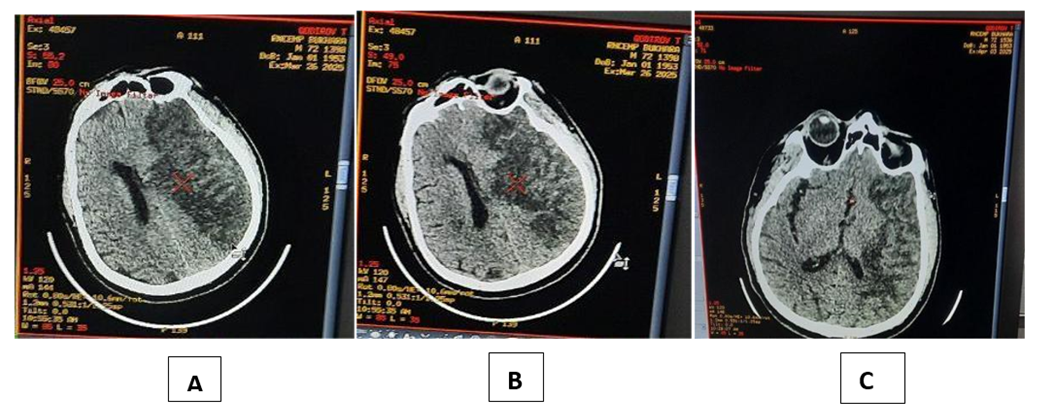

In the main group, by the 15th day after immunocorrectional therapy, there was a significant decrease in the level of cytokines such as il-1β, il-6, il-8 in the central peripheral blood, compared with the indicators on the first day taken. In particular, serum il-1β levels decreased 2.3 times and on the 15th day of treatment were 2.2±0.47 PG/ml compared to 5.06±0.45 PG/ml; il-6 decreased 2.4 times and was 10.9±0.94 PG/ml compared to 26.16±1.3 PG/ml. Il-8 decreased 1.9 times and was 7.9±0.70 PG/ml compared to 15.1 ±0.61 PG/ml. Monitoring serum il-6 levels of patients with ischemic stroke and comparing them with the clinical features of stroke makes it possible to note a number of features of cytokine dysbalance in the acute period of the disease. Regardless of the option of withdrawal of II, on the 1st day of the disease, the amount of IL-6 in the blood serum is higher than that of healthy people and reaches its peak on the 5th-10th days of the disease. At the same time, it has been noted that il 6 levels are directly related to the volume of cerebral infarction – ischemia [2,4,6,8,10,12,14]. The jump in the content of this cytokine is determined by the pathogenetic role of a participant in local and systemic inflammation, accompanied by a tumor around his cerebral ischemia. At the same time, the negative prognostic significance of il-6 as a dangerous marker of the immune system is associated with the activating effect on the severity of the inflammatory process in the brain. Thus, the results of the study of the features of the cytokine profile at the systemic and local level showed that ischemic stroke received inflammation and is accompanied by hypersecretion of anti-inflammatory cytokines, the production of which has significant features in the dynamics of the development of the inflammatory process caused by ischemia (blood thinning) in brain tissues. On the 1st day after ischemia, there was a significant increase in the concentration of cytokines using serum inflammation (il-1β, il-6, il-8). Such production of inflammatory mediators and an increase in the amount of cytokines in the blood serum can be assessed as an adequate initial reaction of the immune system to neuroimaging and the development of brain tumors to brain ischemia.In the 1st day after ischemic stroke, in addition to il-6 and il-8 in dynamics, a slight increase in the amount of cytokines studied in the blood serum was observed, the concentration of which increased by 4-5 times, respectively. In the dynamics of the development of the inflammatory process in the brain, an increase in the production of il-6 and il-8 contributes to a further increase in the permeability of the hematoencephalic barrier, the outflow of neutrophils and, as a result, the development of complications. The direct correlation relationship between detected cytokine levels (il-1β, il-6, il-8), cellular immune system indicators T-lymphocytes (CD3+,CD4+,CD8+) suggests that they play an important role in neural inflammatory developmental pathogenesis in ischemic stroke as a secondary factor, and justifies the feasibility of their study to predict progression and consequences in ischemic stroke. The number of days spent in the intensive care unit depends primarily on the state of the vital systems of the body, and for patients with II, this largely determines the level of cerebral dysfunction. As a result of immunocorrectional therapy, MNT has a decrease in the size of the penumbra zone around ischemia and a decrease in neurodevelopment, which leads to a decrease in brain edema, as a result of which there is an early correction of cerebral dysfunction, which is recorded on the Glasgow scale and MSKT, there is a decrease in the volume of Therefore, the duration of stay in the intensive care unit of the main group of patients was 13.8±3.7 days, and in the comparison group-19.4±3.1 days. In ischemic stroke, when an immunocorrectional treatment method is used using an immunomodulatory drug (Acridopheron), neuronal apaptosis is restricted and intra-cerebral pressure normalization occurs, which leads to a faster recovery of central nervous system functions (Glasgow scale). Reducing the duration of stay in the disability and resuscitation department compared to standard therapy. This makes it possible to draw conclusions about improving the results of treatment against the background of the proposed method of using immunocorrectional therapy, which allows you to influence the pathogenetic joint and the molecular mechanisms of the development of brain tumors and neurodevelopment.An analysis of the MSKT data obtained in patients with ischemic stroke in the study showed that all patients in both groups have cerebral hemispheres and cerebral spinal (column) ischemia in primary Mskt. In addition, the flattening of the owners of the cerebral cortex, the narrowing of the basal cistern were signs of a brain tumor with impaired consciousness. Against the background of immunocorrectional therapy in patients of the main group, MSKT data, for example, the shrinkage of the ischemia zone, the appearance of signs of improvement in cerebral cortex architectonics, basal cisternae and the restoration of normal dimensions of the cerebral ventricles, provided information about the regression of brain tumor. The cellular and humoral immune indicators of these dynamic manifestations, blood cytokines, corresponded to the indicators of positive neurological changes on the Glasgow Scale (Figure 5). | Figure 5. MSKT examination of a patient with ischemic stroke in the main group (during A - Intake, V - 7-day, after S - 15-day). In patients in the comparison group, however, the above changes in cranial MSKT s showed significantly slower than in the main group |

Thus, the results of the study of changes in systemic (serum) and cellular and humoral immune indicators of the cytokine profile showed that in ischemic stroke, inflammation was acquired and is accompanied by hypersecretion of anti-inflammatory cytokines, the production of which has significant properties in the dynamics of the development of the inflammatory process that occurs in ischemic stroke. The first day after cerebral ischemia (acute period) received serum inflammation (il-1β, il-6, il-8) with a significant increase in cytokine concentration. Such hyperproduction of inflammatory mediators was assessed as an adequate initial reaction of the immune system to injury and was explained by the predominance of the local level cytokine concentration - the characteristics of their secretion at MNS. Received inflammation in cerebral ischemia (il-1β, il-6, il-8) a significant decrease in the concentration of cytokines on the 15th day of the disease in the blood serum reflects the severity of the inflammatory process in the brain, an increase in the permeability of the hematocephalic barrier, which is characteristic of severe forms of II, which can serve as a reliable prognostic criterion for. | Figure 6. MSKT examination of a patient with ischemic stroke in the comparison group (A - during admission, V - after day 7, s-after day 15) |